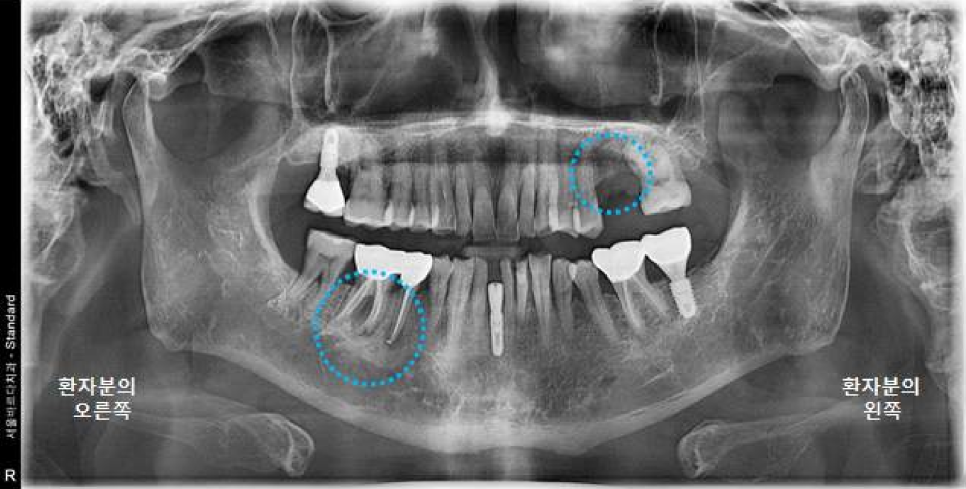

파노라마 엑스레이 상에서 좋지 않게 보이는

오른쪽 아래 어금니도 같이 설명드렸습니다.

오른쪽 아래 어금니 같은 경우는

그냥 눈으로 봤을 때는 크라운 보철이 되어 있기 때문에

상태가 너무 좋아 보이지만

엑스레이상으로 보면 뿌리에 길게 신경치료 한 부분이 보이고

"뿌리 끝 염증으로 주변 뼈가 까맣게 녹고 있는 모습"이 보입니다.

환자분은 현재 왼쪽 위 어금니 통증 때문에

오른쪽 아래는 통증은 크지 않다고 하셨지만

염증은 한번 생기면 사라지지 않고, 계속 뼈를 녹입니다.

일단 오른쪽 아래 큰어금니 염증이 크고

뿌리 부분 뼈를 많이 녹여놓았기 때문에

오른쪽 아래 큰 어금니는 더 이상 뼈를 손상시키기 전에

임플란트를 진행하기로 하 였습니다.

오른쪽 아래 큰어금니 같은 경우에는,

이미 뼈가 많이 손상된 상태이기 때문에

뼈이식과 함께 임플란트를 같이 진행하기로 하였습니다

오른쪽 아래 작은 어금니는 염증이 작게 보이기는 하지만

큰 어금니에 비하여 심하지 않고

환자분 통증이 없기 때문에

일단 큰 어금니 먼저 치료하고 지켜보기로 하였습니다.

(서울바르디치과는 꼭 필요한 진료와 꼭 필요한 뼈이식만을 권해드립니다^^)

<치료 결정>

왼쪽 위 큰어금니 (26번치아) : 임플란트

오른쪽 아래 큰어금니 (46번치아) : 발치 + 임플란트 + 뼈이식